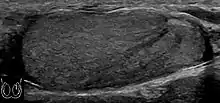

- Fig. 29. Undescended testis. (a) Normal testis in the scrotum. (b) Atrophic and decreased echogenicity of the contralateral testis of the same patient seen in the inguinal region.